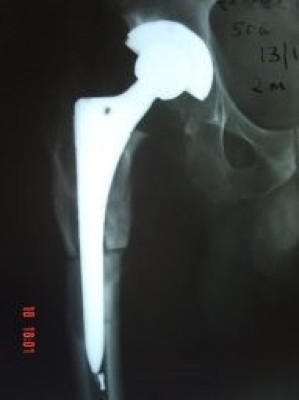

Prótesis Total de Cadera

Envíado por Dr. Ricardo Antonio Gómez G.